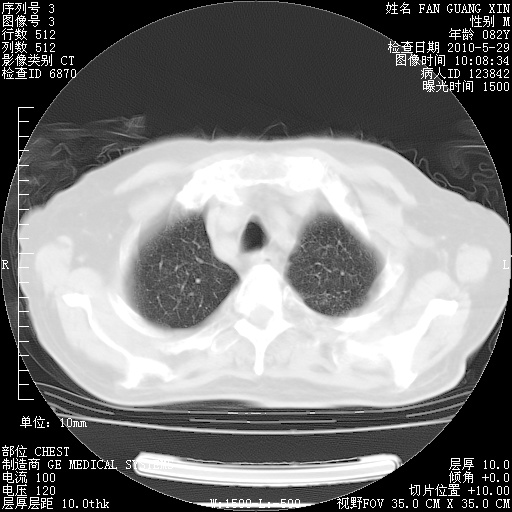

再治疗10天后的肺部CT

从白细胞总数和中性比例看好像合并感染。肺部纹理好像比上次多,支气管炎?其他感染?

阅读此次胸部CT,肺间质渗出性改变较入院时有吸收。目前从体温、白细胞、中性分叶明显增高,肯定存在细菌感染(发生医院感染哦,若无消化道及泌尿系统等感染的依据,肺部感染可能大)。若你院头孢哌酮舒巴坦钠耐药率较高,同意你的方案,若48小时体温仍高,可考虑使用碳青霉稀类抗菌药物,同时可予超声雾化、注意滴数时加大液体量。白蛋白33.30g/L较低哦,需加强营养等支持治疗。